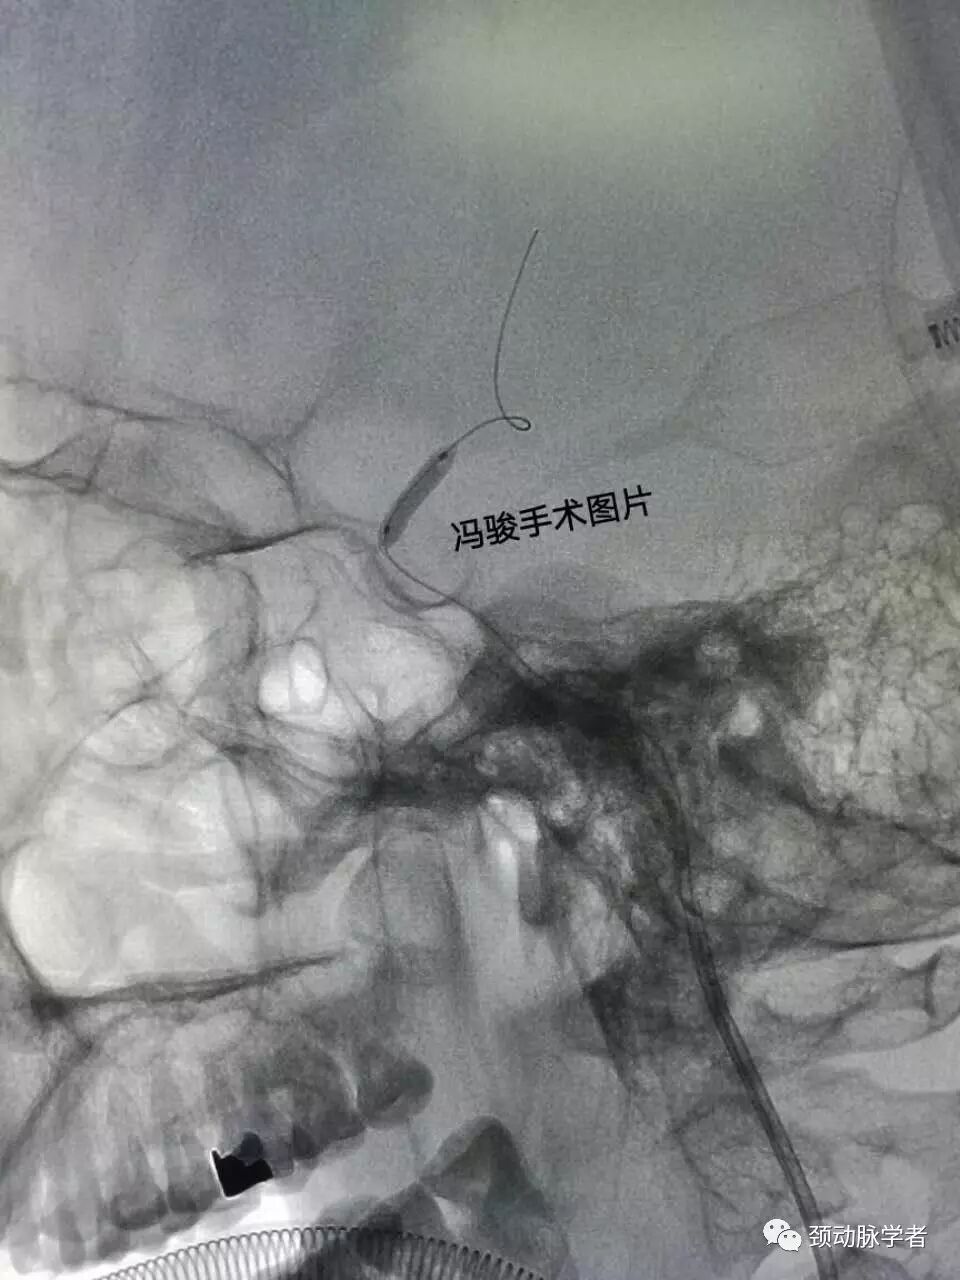

全麻下,guiding置入左颈内动脉海绵窦,造影显示,床突上段的确99%线样狭窄。

微导丝轻巧地通过病变,置入左侧大脑中动脉分支,用2.0-12mm球囊渐进性预扩。